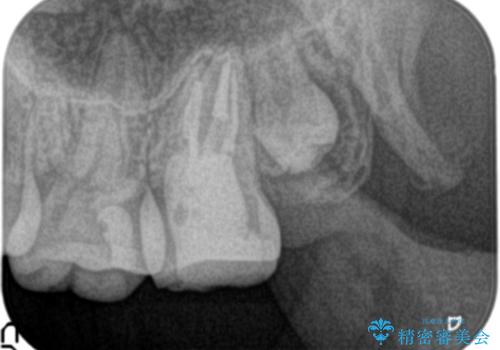

- 他院にて奥歯の治療をしても痛みが引かずに、ラバーダムの存在を知り、無菌的な治療を行える病院を探して当院を受診されました。

根管治療~フルジルコニアクラウンにて修復しております。

治療前には打診、圧痛がありましたが治療後には症状が消失し、3ヶ月後のレントゲンでも透過像の縮小を認めています。

治療介入時、根管内部にはカリエスや異物が存在する状態でしたが適切な処置を行うことで症状を改善することができました。